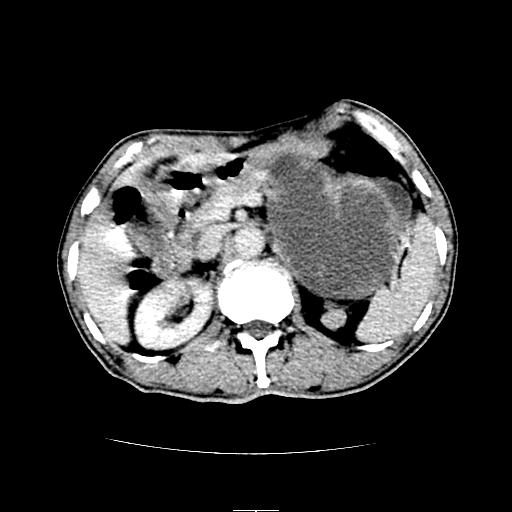

标题: CT6969:腹部,某男 34岁,腹痛治疗半月无效 [打印本页]

标题: CT6969:腹部,某男 34岁,腹痛治疗半月无效

左上腹胃、脾及胰腺间巨大囊性占位性病变,内见多数薄隔,有轻度强化,明显占位效应,胰腺及左肾结构清楚,明显向后下方推压 移位。左肾见一小囊肿.多考虑:1 网膜巨大囊肿。2 左肾小囊肿。

1胃脾胰之间一巨大囊性影,胃明显向前推移,胰体尾部似肥大,考虑囊性影来源于胰腺(假性囊肿?)2左肾小囊肿。

左上腹囊性占位,虽与胰腺分界不清,胰尾似乎受压前移,病灶最大截面并不在胰腺水平,考虑来源于网膜可能性大吧,应再详细追问病史.

考虑胰腺巨大囊肿,左肾低密度灶从形态和强化方式看不象囊肿,应考虑肿瘤。

左上腹胃、脾及胰腺间巨大囊性占位性病变,其内见多数薄隔,有轻度强化,明显占位效应。左肾见一小囊性变。

左肾囊肿;网膜巨大囊肿。